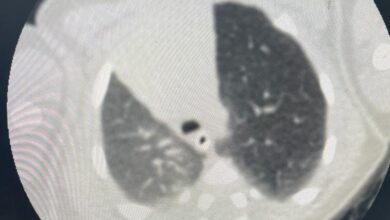

فريق طبي “أبها الخاص” ينهي معاناة أربعيني

أحوال – عسير – شذى عسيري: قرر فريــق طبـي بمستشفى أبها الخاص إنهاء معاناة مريض يبلغ من العمر 48 عاماً كان يعاني لمدة 6 أشهر من آلام شديدة بالبطن يصاحبها…